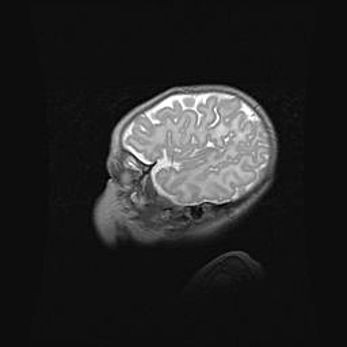

Неполная лизэнцефалия (пахигирия). Открытая гидроцефалия.

Возраст: 17 дней

Вес: 3110 г

Пол: мужской

Окружность головы: 33,5 см

Срок гестации: 35-36 недель

Лизэнцефалия—недоразвитие корковой пластинки и мозговых извилин в результате нарушения миграции нейронов коры. Поверхность мозговых полушарий гладкая. Микроскопически выявляется отсутствие нормальных слоев коры и скопление групп нейронов в подкорковом белом веществе.

Пахигирия—уменьшение числа вторичных извилин. В пораженном полушарии нервные клетки образуют толстый недифференцированный слой с неправильно расположенными нервными волокнами и группами гетеротопных клеток. Нервные клетки незрелые. Белое вещество истончено. При этом нередко аномально развит корково-спинномозговой путь.